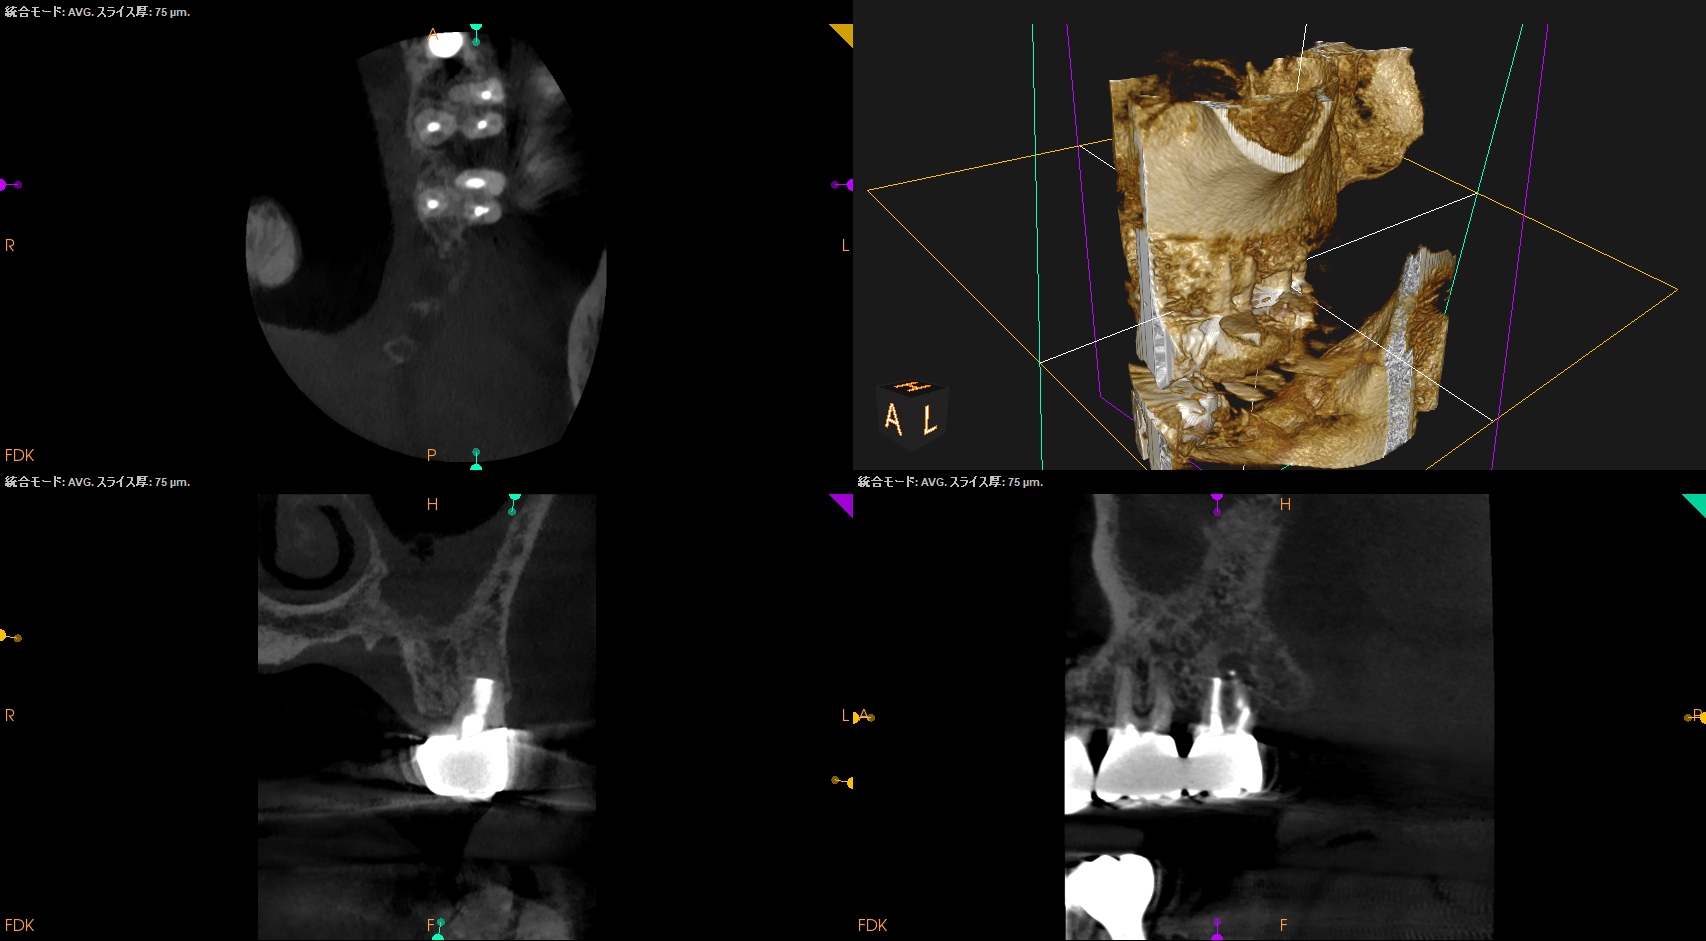

CBCTも撮影した。

MB

DB

P

術前と比較した。

ということで、臨床症状と術前/術直後の骨欠損(根尖病変)も消失し、歯槽骨が回復したため, この日で終診とさせていただいた。